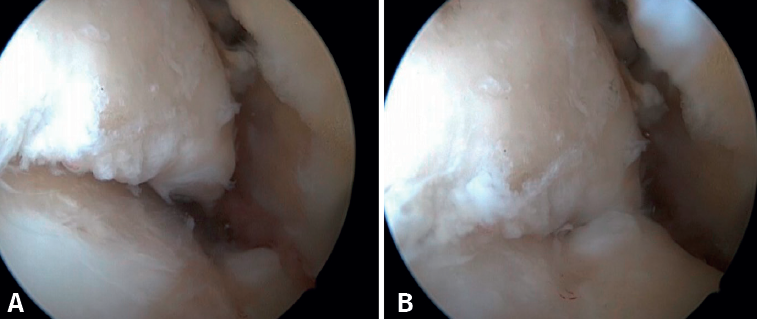

Bony AAI due to osteophytes has also been linked to the presence of chronic instability. It has been postulated that altered joint kinematics secondary to ligament insufficiency favors the development of osteophytes in the anterior region of the tibia and talus(36,37). Recent studies have questioned the theory of repeated capsular traction as the origin of osteophytes in sports(38), as it is easily demonstrated that osteophytes are located intra-articular within the capsular insertion, in the context of ankle arthroscopy (Figure 2). Therefore, ankle dorsiflexion arthroscopy is essential to safely resect osteophytes without damage to the capsule or overlying structures, whereas the classical traction technique (invasive or otherwise) would make resection extremely difficult, and is thus not recommended nowadays for routine use(3,39). Vega distinguished between two types of osteophytes(3), according to whether they are caused by repetitive trauma (peak-shaped) or instability (visor-shaped). The concept of micro-instability is associated with repetitive micro-trauma, which could be the origin of osteophytes with this characteristic morphology (Figure 3).

Resection of the osteophyte is performed by displacing from the top, and gradually reducing it until the joint zone is reached (Figure 2). A basket forceps can be used to resect the area closest to the joint (Figure 5). It is often useful to exchange the viewing and working portals in order to visualize and completely resect the osteophytes. In the case of soft tissue impingement, a 3.8 or 4 mm synoviotome is usually sufficient. The vaporizer is useful in the case of compact impingements, typical of post-traumatic conditions or re-interventions, and also for delimiting the bony part of the osteophyte before resection.